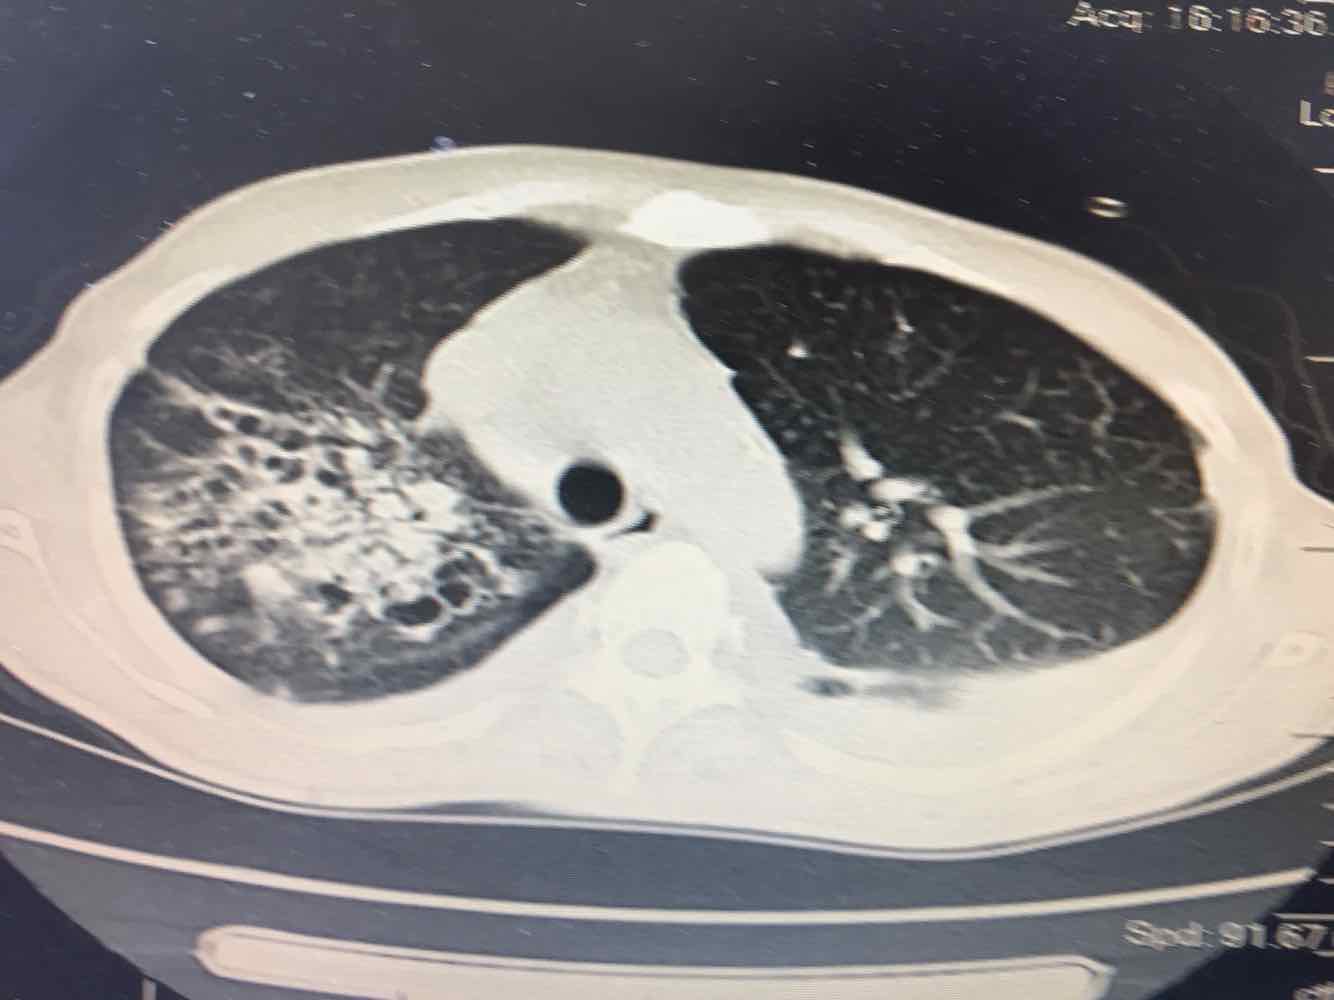

女,51岁,支气管扩张病史多年。慢性咳嗽咳痰喘息30年,加重1个月,无发热,气短为主,痰液不多,上腹不适,少尿。双肺干湿罗音。